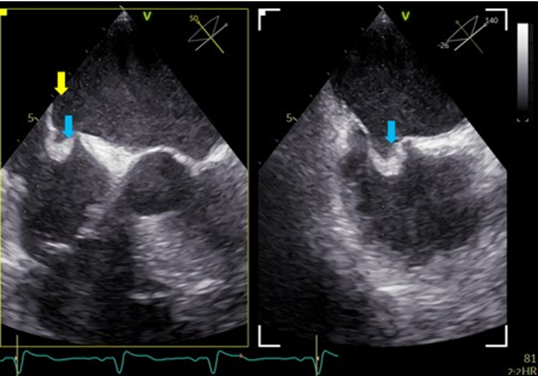

No atrial fibrillation (AF) was found within 93 hours of in-hospital monitoring. Transthoracic echocardiography (TTE) revealed a reduced ejection fraction of 25% with global hypokinesia. Transesophageal echocardiography (TEE) showed an ASA bulging into the right atrium (9 x 10 x 9 mm) and containing thrombotic material on the left atrial side (Figure 2). There was no evidence of a PFO with or without Valsalva manoeuvre.

Figure 2: Description of ASA. TOE, mid-oesophageal, 50° and 140°. The two planes show perpendicular views of the ASA. The ASA opens to the left atrium and was filled with thrombus formation (blue arrows) as well as with smoke (yellow arrow). The linked cine loop shows the same views in the moment when rightheart contrast agent was administered. There was no contrast agent detectable in the left atrium, thus excluding an interatrial shunt.